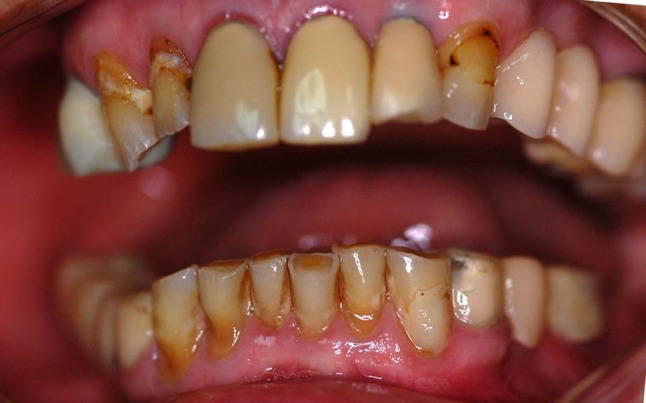

An 86-year-old partially edentulous woman sought oral treatment with complaints of poor aesthetics and movement of her existing prosthesis during function (Fig. 1). Anamnesis, clinical examination, and panoramic radiography were used to diagnose this patient (Fig. 2). The patient had controlled hypertension, and displayed no symptoms of temporomandibular dysfunction, dental pain or xerostomy, and presented with satisfactory oral hygiene.

Fig. 1.

Clinical oral condition